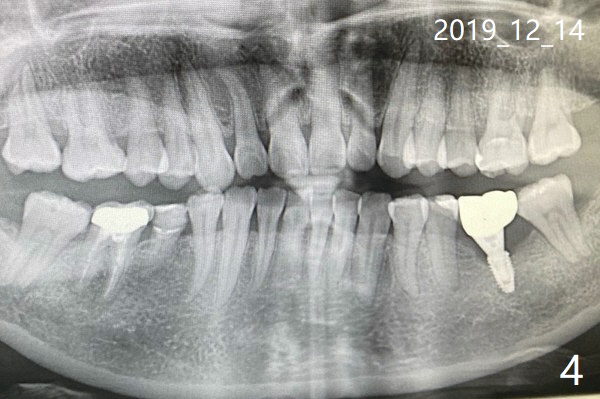

I just forward my wife's email to you.  Unfortunately her planted tooth got off from the foundation (Fig.1,2 (7 months post cementation)).  We have visited several clinics in Beijing.  They do not have the tool to handle it because the model you used is not popular in Beijing.  Would you like to lend your tool to us? We will send it to you once repair is done.  December 1, 2019, 07:37:14 AM EST

这边我找到有Neo种植体的诊所了,可那医生说应该植骨,重种。您能把我在美国时刚做完植体和装上牙冠后的x片发给我吗?我也把12月1号,8号和14号的x片发给您(图三至五). 另外,植体里的螺丝会磨没了吗? December 14, 2019, 3:21:23 AM EST